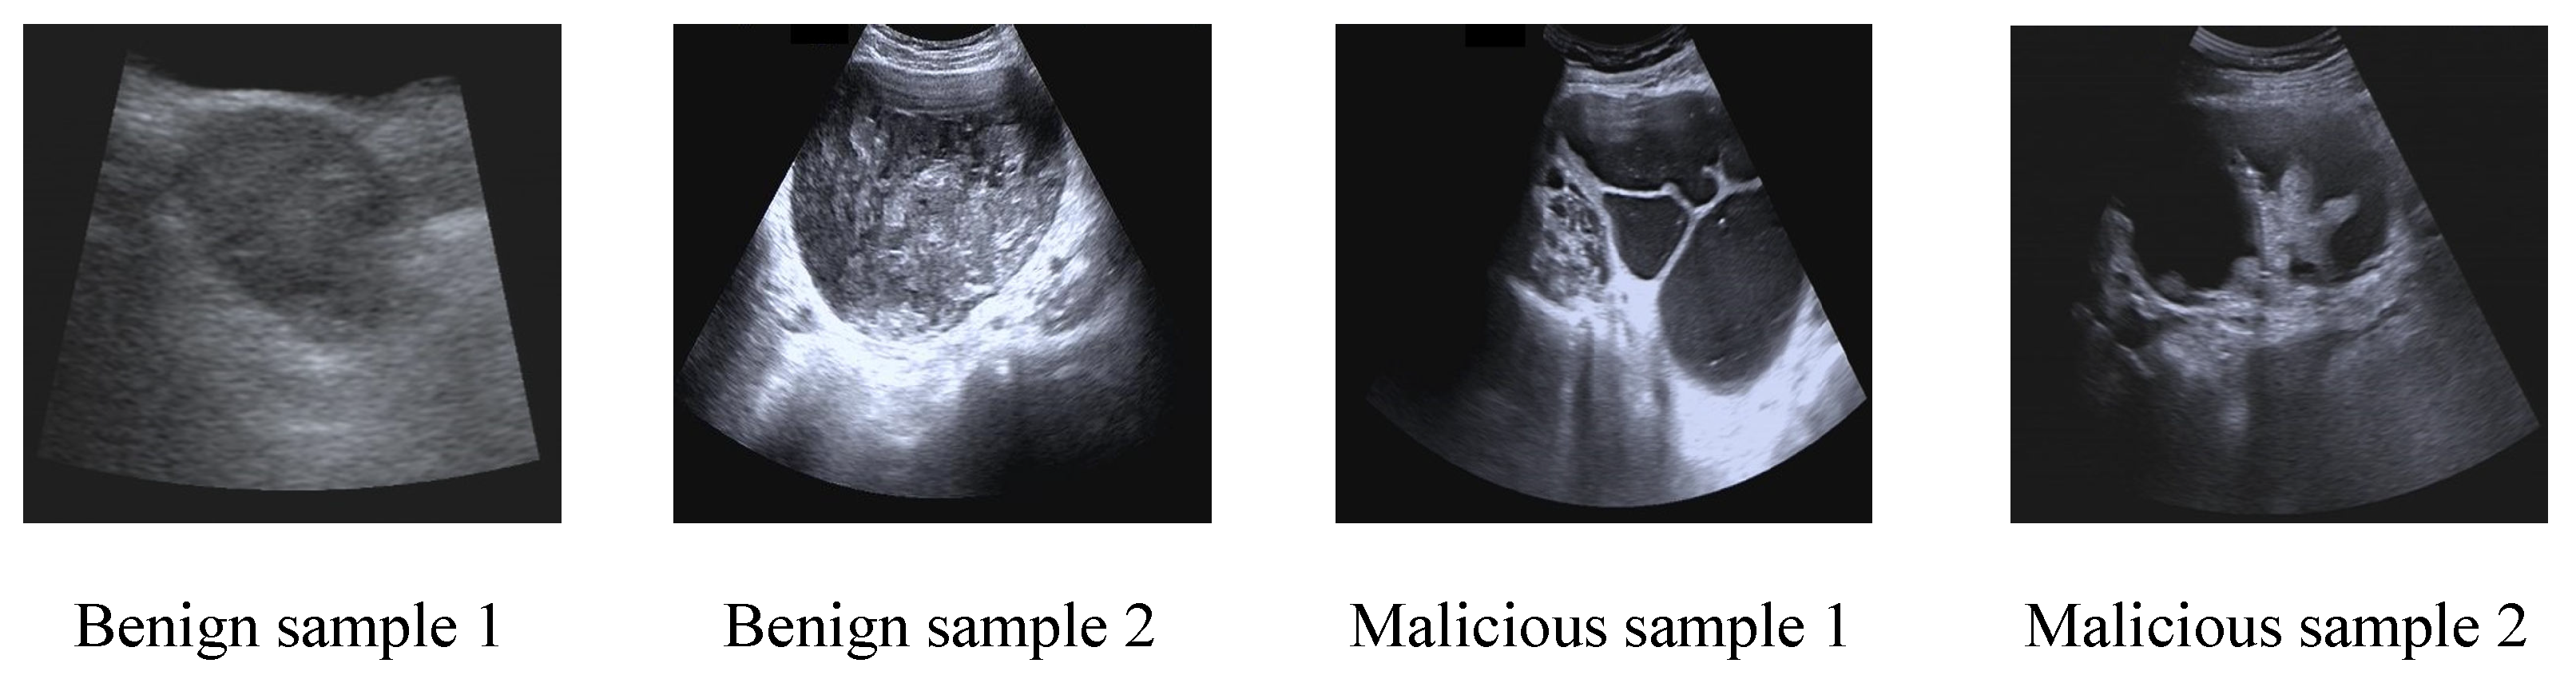

3.1. Data Collection